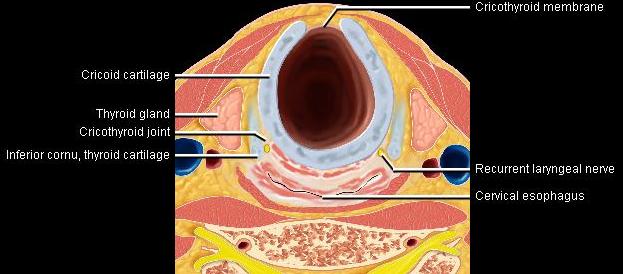

Phonation and dysphagia involve multiple coordinated structures in the larynx and pharynx. Radiation induced dysphagis appears to be related to dose to the phyaryngeal constrictor muscles and specific regions of the supraglottic and glottin larynyx.

Speech is impacted by doses to the epiglottis, base of tongue, aryepiglottic folds, false vocal cords upper esophageal sphincter and cricoid cartilage.

The mean laryngeal volume receiving > 50 Gy was a predictor of laryngeal edema. Vocal functions are usually well preserved with doses of 60 - 66 Gy. Dornfeld found a strong correlation between speech quality and dose to the ariepiglottic folds, pre-epiglottic space, false vocal cords and lateral pharyngeal walls at the level of the false vocal cords. A steep decrease in dose function was noted when doses exceeded 66 Gy.